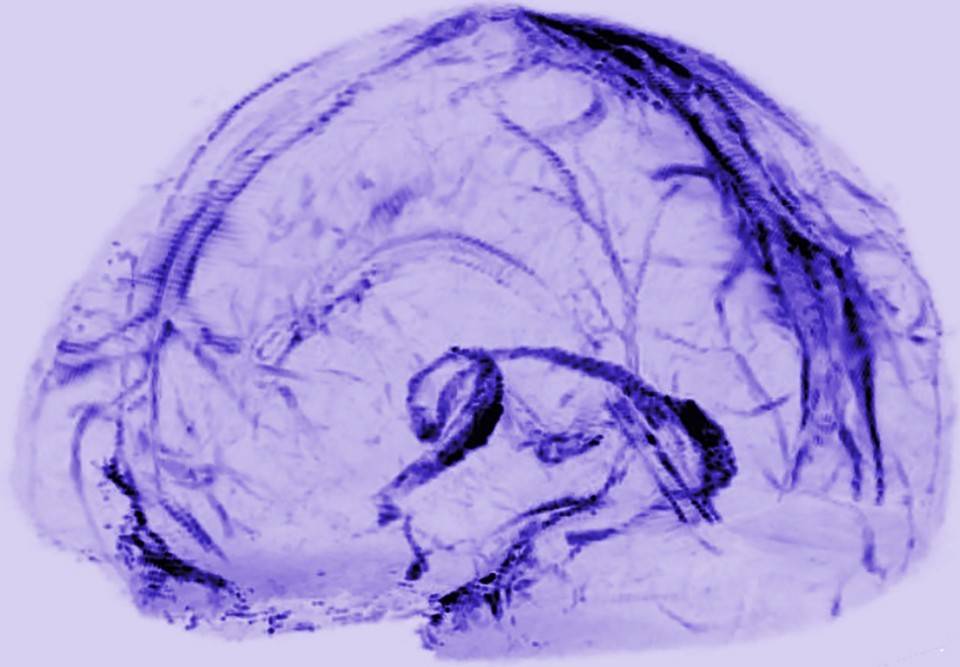

一直以来,医学生接受的教育是,人类头部不存在淋巴系统。本月,美国国家神经病学和中风研究所(the U.S. National Institute of Neurological Disorders and Stroke)的研究人员的发现改变了这一传统观念。在他们公布的人脑淋巴管成像图中,这些管道第一次呈现在我们面前。

而雷希本月的发现意义同样重大,雷希的团队不仅在人脑中证明了淋巴管的存在,更详细地描述了这个系统的细节。

雷希团队为我们呈现出了人类大脑内的“排污系统”

人脑中淋巴管一直没有被发现的原因可能是,它们被包裹在一层很厚的硬脑膜中,而且与粗大的血管交织着,而血管才是核磁共振成像的信号的主要来源。此外,雷希还补充了一条很重要也很明显的原因:“也可能根本没有人去刻意寻找它们。”